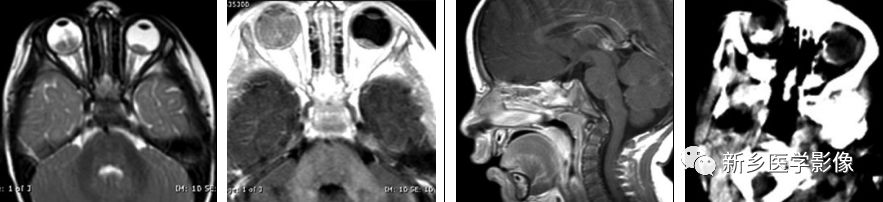

畸胎瘤

松果体区示颅内畸胎瘤最常见的发生部位。松果体畸胎瘤仅见于年轻男性。在MRI T1WI及T2WI上呈混杂信号。局部脂肪在T1WI上表现为高信号。

横断位T1WI示一混杂信号肿块伴多囊变,注意病灶右后方局部高信号的出现,符合脂肪。在CT上病灶内可见钙化,在MRI无表现。横断位T1WI+C示多环强化。